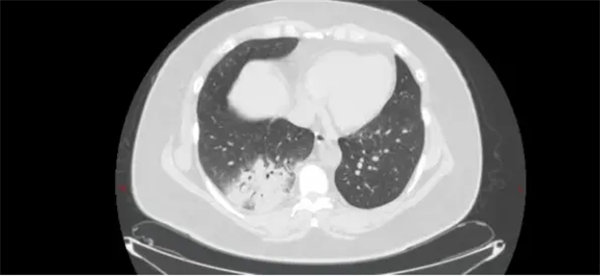

51歲的王女士(化名)持續(xù)發(fā)熱5天,體溫最高達(dá)39.5℃,伴全身乏力、關(guān)節(jié)肌肉酸痛。在外院輸液治療3天后仍反復(fù)發(fā)熱,遂轉(zhuǎn)至我院呼吸與危重癥醫(yī)學(xué)一科住院。主治醫(yī)師李旭東接診后,發(fā)現(xiàn)其胸部CT及血常規(guī)等檢驗(yàn)結(jié)果提示非典型病原菌感染,結(jié)合患者家中養(yǎng)有鸚鵡的情況,高度懷疑鸚鵡熱衣原體肺炎。學(xué)術(shù)主任王惠霞、科主任魏勝全與副主任醫(yī)師賈汝臻綜合患者長期養(yǎng)鸚鵡的愛好、病史、查體、CT片及相關(guān)檢驗(yàn)結(jié)果,確認(rèn)臨床判斷。